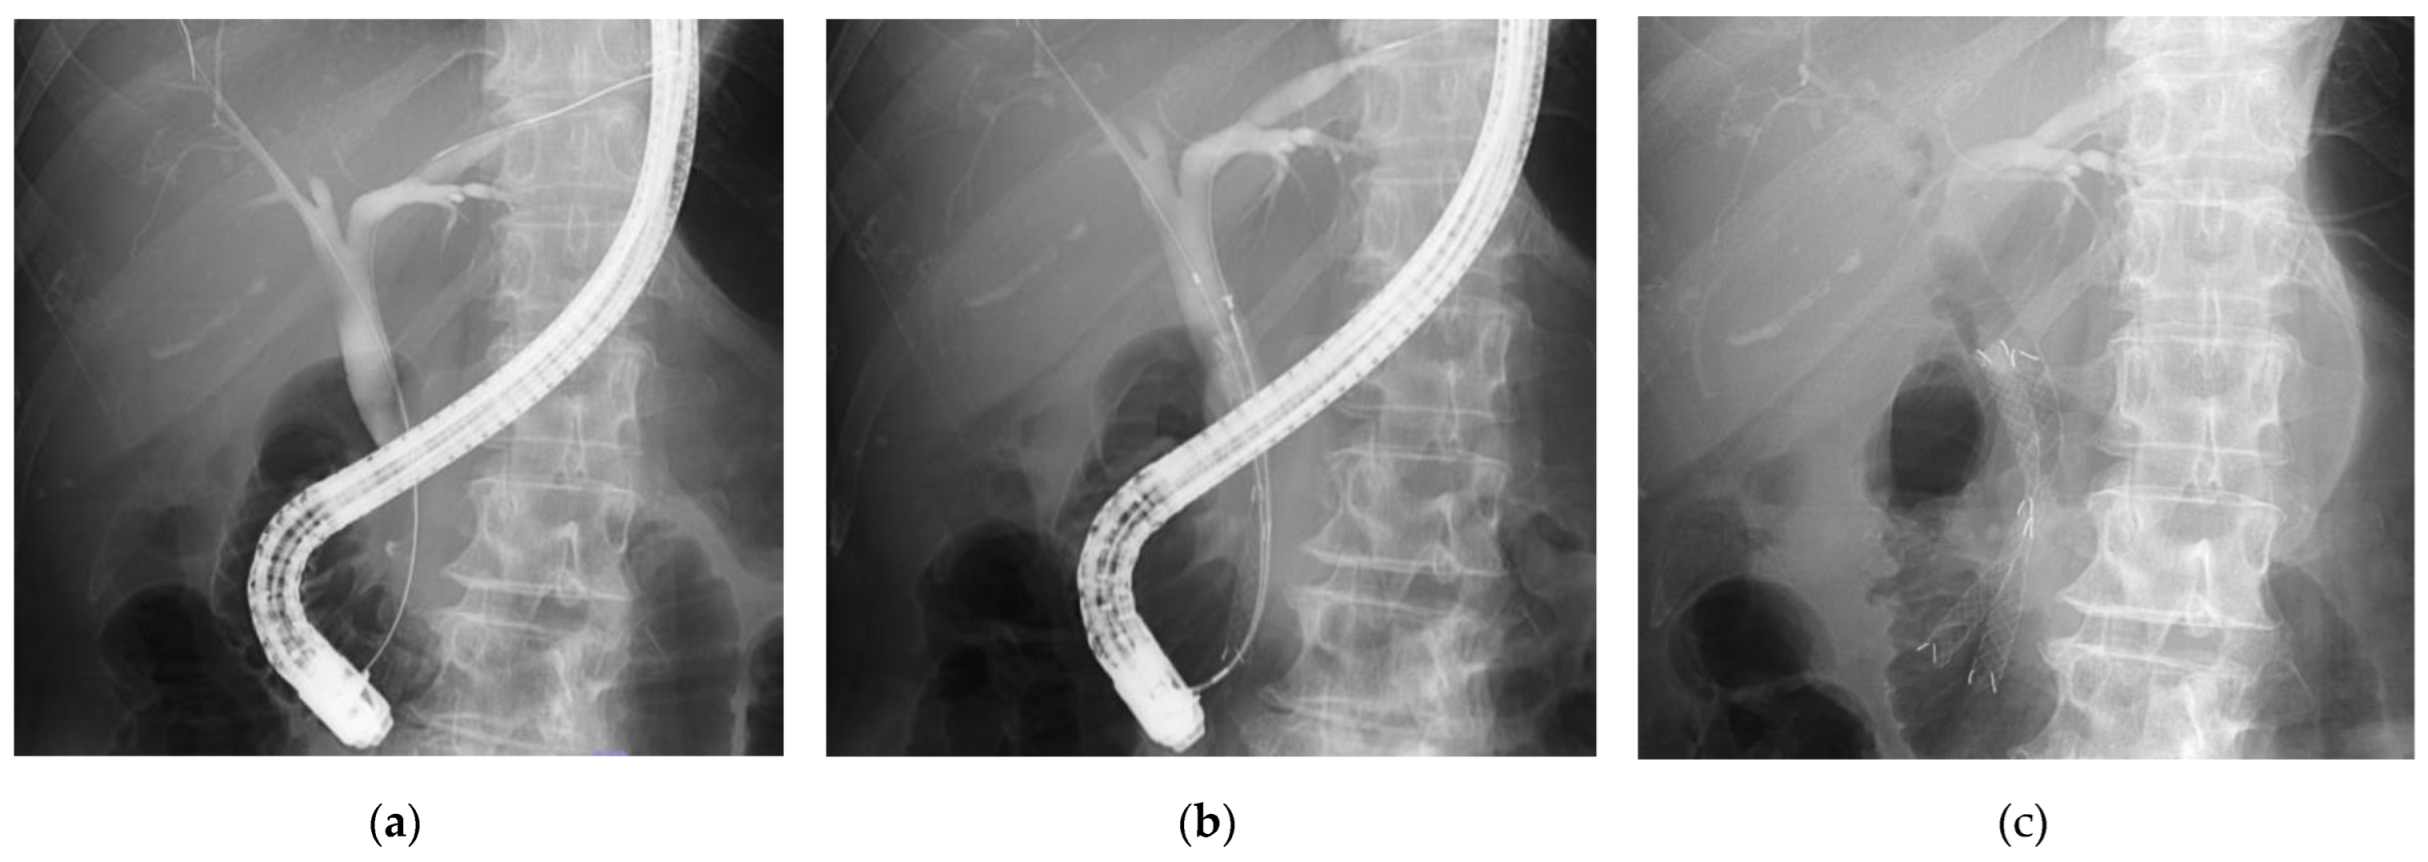

2.3. Procedure for DSS